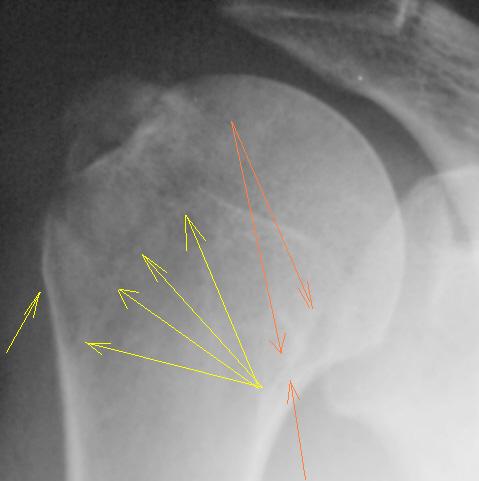

Вот то, что отмечено желтыми стрелочками на последней серии снимков - и есть отрыв большого бугорка. Такой большооооой отрыв большоооооооого бугорка.

Согласен с Вами Анна. "Ну очень большой".

С большим бугорком более-менее понятно. Вопрос: где малый?